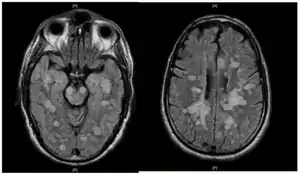

Fulminating ADEM showing many lesions. The patient survived, but remained in a persistent vegetative state

ADEM produces multiple inflammatory lesions in the brain and spinal cord, particularly in the white matter. Usually these are found in the subcortical and central white matter and cortical gray-white junction of both cerebral hemispheres, cerebellum, brainstem, and spinal cord,[16] but periventricular white matter and gray matter of the cortex, thalami and basal ganglia may also be involved.